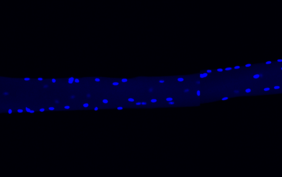

Gewöhnlich besitzt jede Zelle genau einen Kern. Nicht so die Muskelzellen unserer Skelettmuskeln: In einem vergleichsweise riesigen Zytoplasma enthalten diese langen, faserigen Zellen Hunderte von Kernen. Inwieweit sich die Kerne einer einzelnen Muskelfaser hinsichtlich ihrer Genaktivität voneinander unterscheiden und welche Auswirkungen das auf die Funktion des Muskels hat, war bislang kaum bekannt.

„Eine einzelne Muskelzelle kann durch die Heterogenität ihrer Kerne fast wie ein Gewebe, das aus ganz unterschiedlichen Zelltypen besteht, agieren – und so ihren zahlreichen Aufgaben wie der Kommunikation mit Nervenzellen oder der Produktion von bestimmten Muskeleiweißen nachkommen“, erläutert einer der beiden Erstautoren der Studie, Dr. Minchul Kim, Postdoktorand in Birchmeiers Team. Kim hat die meisten experimentellen Arbeiten der Studie übernommen.

Schon vor der Studie war bekannt, dass in Kernen, die sich in der Nähe einer Nervenfaser und ihren Synapsen befinden, andere Gene aktiv sind als in den restlichen Kernen. „Wir haben nun jedoch viele neue Arten spezialisierter Kerne entdeckt, die alle ganz bestimmte Genexpressionsmuster aufweisen“, berichtet Kim. Einige dieser Kerne befinden sich gehäuft nahe zu anderen Zellen, die an die Muskelfaser angrenzen: zum Beispiel Zellen der Sehne oder des Perimysiums, einer Bindegewebshülle, die mehrere Muskelfasern in einem Bündel zusammenfasst.

„Andere spezialisierte Kerne steuern anscheinend den lokalen Metabolismus oder die Proteinsynthese und sind in der Muskelfaser verteilt“, sagt Kim. Was genau die in den Kernen aktiven Gene jeweils bewirken, ist allerdings noch nicht ganz klar. „Wir sind auf hunderte Gene gestoßen, die offenbar in bislang völlig unbekannten kleinen Gruppen von Kernen in der Muskelfaser angeschaltet werden“, berichtet Birchmeier.